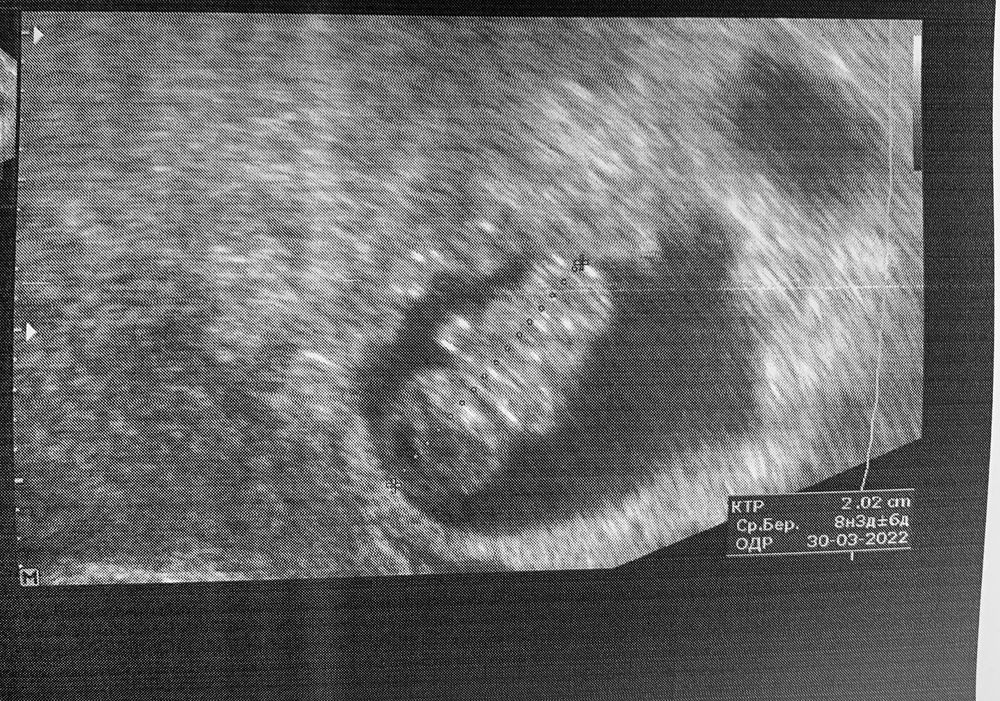

8+5 недель УЗИ

Ленка, по переносу 8+5 недель. По узи и таблицам ктр 8+3

Kate Agaeva, странно, на моем узи в 8+4 при КТР 20 стоит 8 недель и 4 дня, у вас даже чуть больше чем 20.

И в моей табличке 20 мм - это 8+4)

А какой у вас срок по переносу? Я была в 8+4 по переносу и КТР был 20 мм - это было прям ровно на 8+4. Желаю легкой беременности и родов в срок здорового малыша!